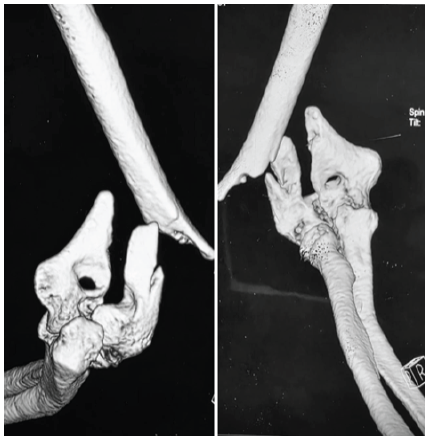

A woman in her 30s from South Asia presented to our tertiary orthopedic unit with persistent pain, restricted range of motion, and functional impairment in her left upper limb. These symptoms had been present for several months following surgical fixation of a distal humerus intercondylar fracture sustained after a fall on an outstretched hand while descending stairs. At the time of injury, she was evaluated at a local trauma center, where radiographs revealed a displaced intercondylar distal humerus fracture with a concurrent fracture of the proximal shaft of the ipsilateral ulna (Fig. 1). She underwent open reduction and internal fixation using dual plating for the distal humerus and plating for the ulnar fracture (Fig. 2). The limb was immobilized in a splint for 10 days, followed by supervised physiotherapy. The ulnar fracture showed progressive healing and achieved union by 3 months post-operatively.

Figure 1: Pre-operative 3D computed tomography reconstructions showing a displaced intercondylar fracture of the distal humerus with associated ipsilateral proximal ulnar shaft fracture.